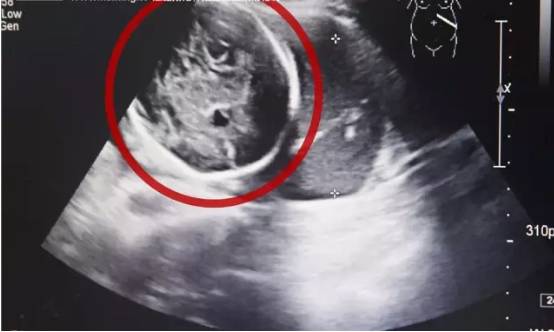

医生确诊小芳为经B超检查,小芳竟然已经怀孕了,而且胎儿已经长到了6个多月!但是让人震惊的是胎儿并没有长在子宫里,而是长在了腹腔内。“腹腔妊娠”,也就是宫外孕的一种,这种发病率约为1:15000,母体死亡率约为5%,胎儿存活率仅为1%的罕见妊娠,竟然发生在了她的身上,而且小芳已经出现肚子疼痛,情况十分紧急!

医院医生解释道,这种异位妊娠就像体内的一个‘定时炸弹’,随时可能破裂大出血危及生命。”

医生一边安抚小芳,一边紧急安排检查和会诊。经医生进一步检查发现,胎儿已经不幸死亡,而小芳的情况也十分危险如果不及时手术,随时可能出现大出血,危及生命。  医院立即安排小芳尽快接受手术治疗。